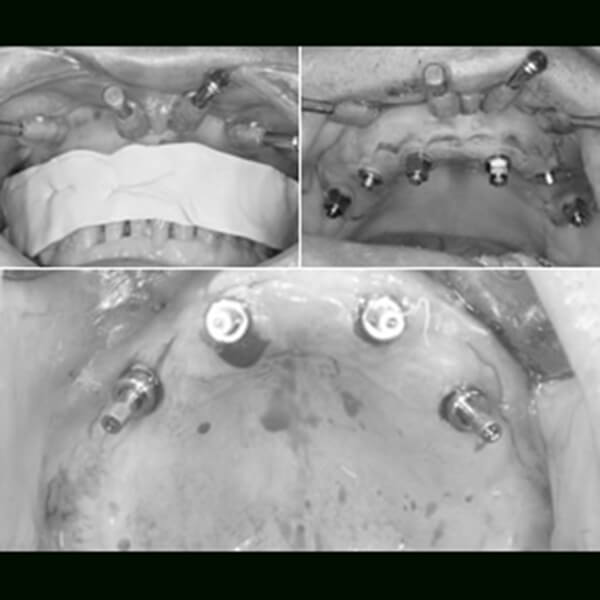

フラップスで手術

ノーベルガイドを用いて6本のインプラントをフラップスで手術

術後

(その日の内に仮歯を装着)

最終的なブリッジ

約半年後に美しい仕上がりの最終的なブリッジが入ります

サージカルテンプレートを用いたフラップレスで、確実でより安全に

インプラント

CTスキャンデータ、3Dシミュレーションソフトを使いインプラントの埋める位置を確認します。

そのデータをもとに、精巧なノーベルガイドを用いたサージカルテンプレートを作製。シミュレーションにより算出したインプラントの埋入の位置や角度が正確にわかりますので、安全で確実な手術ができます。

オペはこの、サージカルテンプレートを歯肉へ装着して、一部分に小さな穴を開けてインプラントを埋入します。

ほとんどの歯肉をきりませんので術後の腫れ・痛みをおさえることができます。